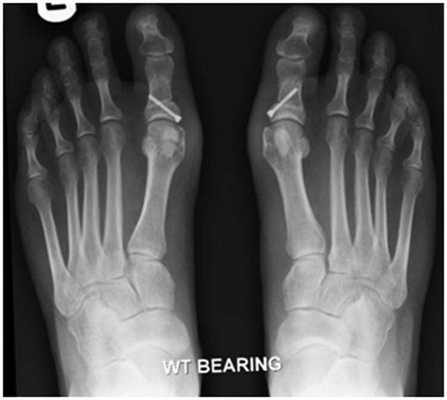

По статистике, Hallux Valgus разной степени выявляют у 100% пациентов с поперечным плоскостопием. Во время хирургического вмешательства врачам приходится одновременно устранять обе патологии.

SCARF

Z-образная остеотомия Scarf – это золотой стандарт лечения вальгусной деформации. Она позволяет установить головку плюсневой кости под нужным углом. В ходе хирургического вмешательства врачи также убирают деформацию суставной капсулы и меняют направление некоторых сухожилий.